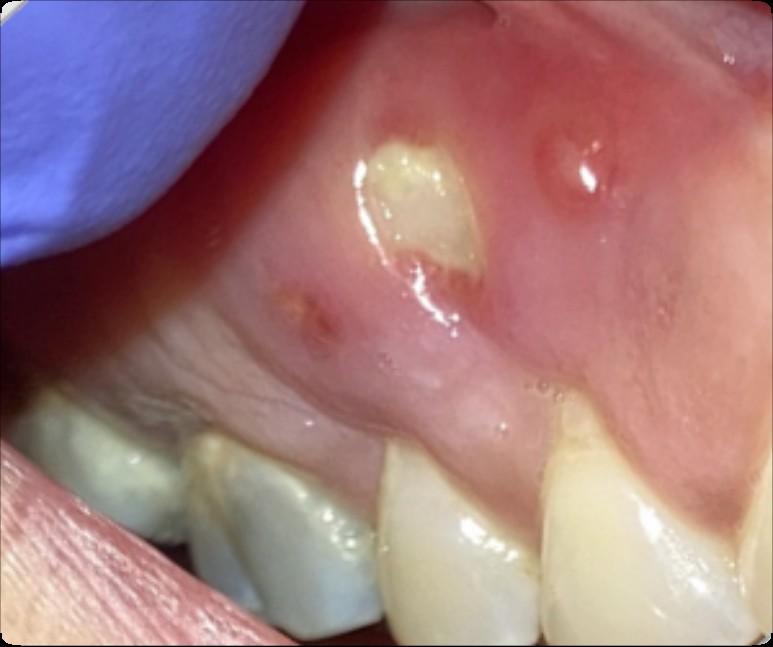

Treatment Related Oral Complications

Due to both direct damage to oral tissues secondary to cancer treatment and indirect damage due to regional or systemic toxicity

• Mucositis (oral lesions) -> Managing Oral Pain

• Oral infections -> Prevention

• Poor oral hygiene -> Basic Oral Care

The Role of Basic Oral Care (BOC)

• Reduces the risk and severity of oral complications.

• Improves the likelihood that the patient will successfully complete planned cancer treatment.

• Prevents, eliminates, or reduces oral pain.

• Minimizes oral infections that could lead to potentially serious systemic infections.

• Prevents or minimizes complications that compromise nutrition.

• Improves the quality of life.

Elad S, Raber-Durlacher JE, Brennan MT, et al. Basic oral care for hematology-oncology patients and hematopoietic stem cell transplantation recipients: a position paper from the joint task force of the Multinational Association of Supportive Care in Cancer/International Society of Oral Oncology (MASCC/ISOO) and the European Society for Blood and Marrow Transplantation (EBMT). Support Care Cancer. 2015 Jan;23(1):223-36.